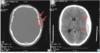

Diagnosis?

Epidural hematoma

Most likely cause?

Rupture of the **middle meningeal artery**; often secondary to pterion skull fracture

Subdural hematoma

Etiology/cause?

**Rupture of bridging veins** (can be acute or chronic) * Hemorrhage crosses suture lines; poor prognosis